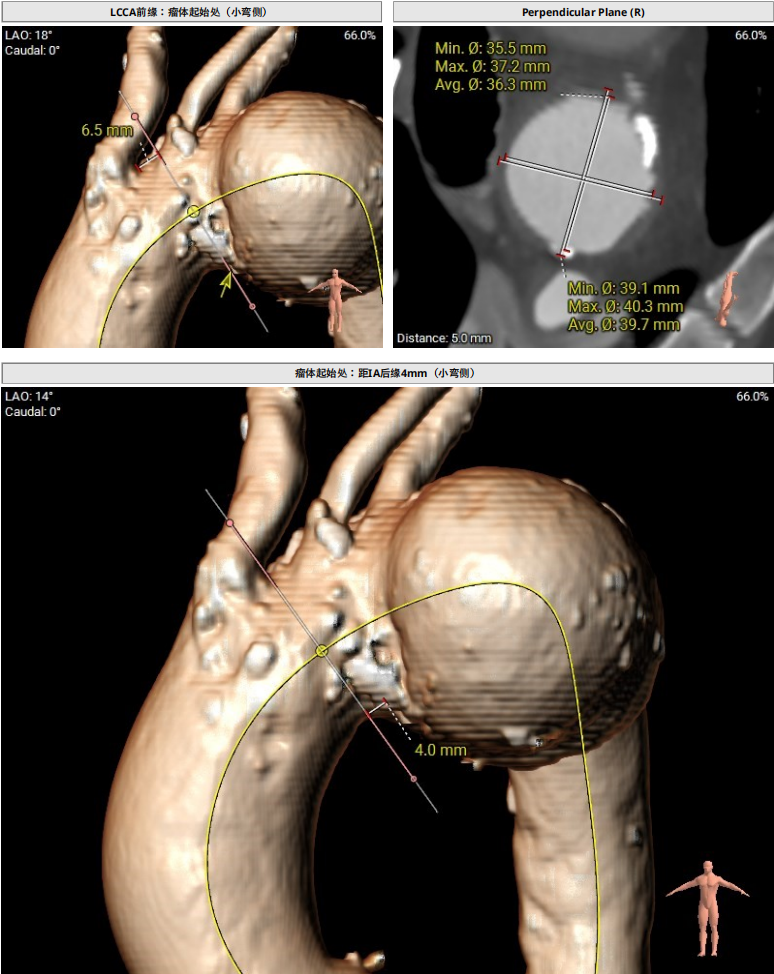

该患者主动脉弓部瘤,瘤体起始于LCCA前缘,距IA后缘4mm(小弯侧),瘤体最大处直径67mm,左椎优势。

CTA显示,患者主动脉弓部瘤,瘤体起始于LCCA前缘,距IA后缘4mm(小弯侧),瘤体最大处直径67mm